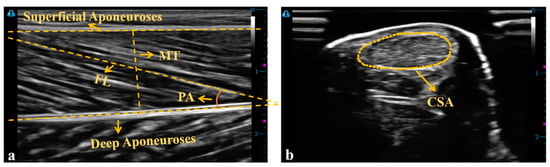

2.2. Instrumentations

2.4. Data Analysis

| CSA (mm2) | 55.82 ± 11.52 | 56.13 ± 8.29 | 51.95 ± 6.95 | 0.387 | 0.068 |